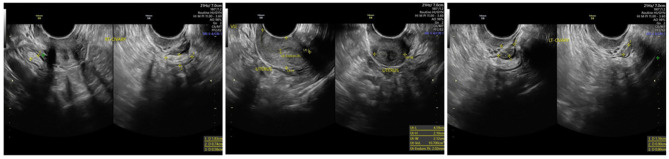

Case illustration: A 33-year-old woman with a history of irregular menstruation since adolescence was referred for evaluation of uterine hypoplasia and chronic anovulation. Clinical findings included short stature, but no webbed neck or congenital heart defects, making this an atypical presentation of Turner syndrome. Transvaginal ultrasound revealed a small uterus and bilateral streak ovaries. Hormonal evaluation showed elevated FSH levels consistent with hypergonadotropic hypogonadism. Diagnostic laparoscopy confirmed bilateral streak ovaries with normal appearing uterus and fallopian tubes. Chromosomal analysis using G-banding revealed a 46,X,i(Xq) karyotype, indicating an isochromosome Xq abnormality, a recognized variant of Turner syndrome. This genetic alteration explains her ovarian dysfunction and infertility, highlighting the importance of chromosomal evaluation in cases of primary ovarian insufficiency.